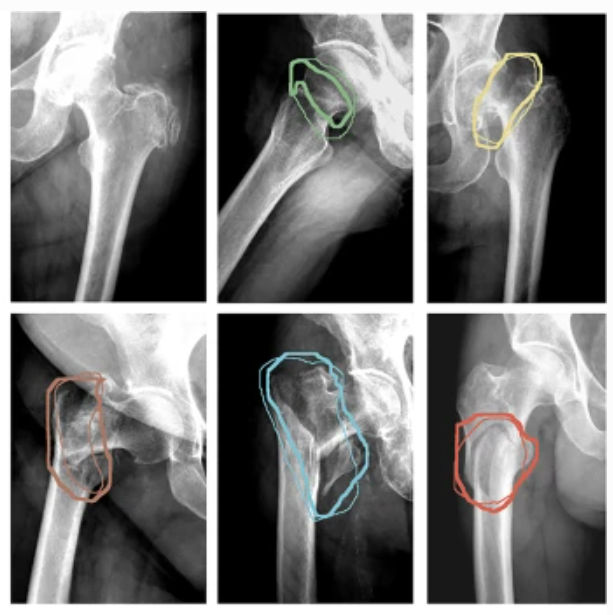

Researchers have developed an innovative artificial intelligence system that can detect, classify, and segment hip fractures in x-ray images with high precision. Trained on thousands of annotated radiographs, the model identifies the exact location and type of fracture—whether in the femoral neck, pertrochanteric, or subtrochanteric region—and grades its severity using established medical scales. Unlike previous methods that only labeled entire images, this approach highlights the specific fracture area, offering clearer visual cues for diagnosis. With an AUC of over 96% in fracture detection and 86% in classification, the system shows promise as a valuable tool for improving diagnostic confidence and supporting clinical decision-making.